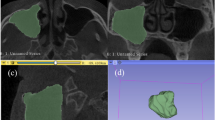

In this study, linear data of the maxillary sinus in the population of northwest China by using Cone-Beam Computed Tomography (CBCT) were collected and utilized to develop logistic, K-Nearest Neighbor (KNN), Support Vector Machine (SVM) and random forest (RF) models for sex estimation with R 4.3.1. CBCT images from 477 samples of Han population (75 males and 81 females, aged 5–17 years; 162 males and 159 females, aged 18–72) were used to establish and verify the model. Length (MSL), width (MSW), height (MSH) of both the left and right maxillary sinuses and distance of lateral wall between two maxillary sinuses (distance) were measured. 80% of the data were randomly picked as the training set and others were testing set. Besides, these samples were grouped by age bracket and fitted models as an attempt.